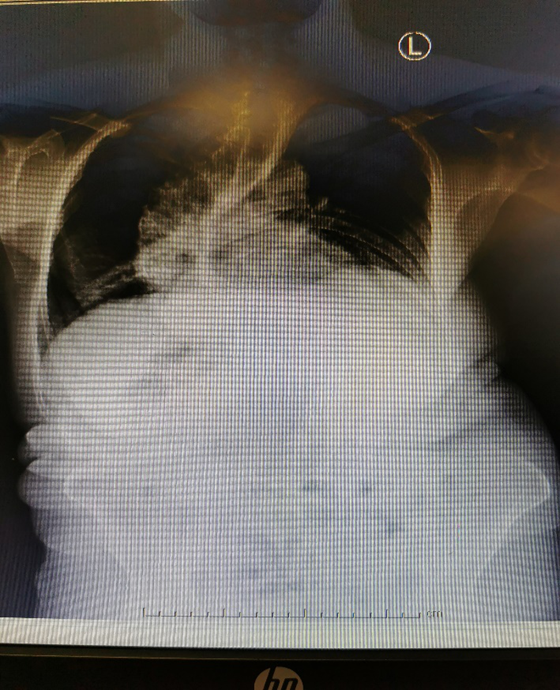

经过普外科医生体格检查,雷阿姨患的是混合痔,需要进行手术治疗。摆在麻醉医生面前的难题是:曾奶奶身高仅一米四,有严重的脊柱侧弯畸形,一侧剃刀背像驼峰一样高高隆起,脊柱正常生理性结构几乎不复存在,实施椎管内麻醉存在巨大挑战。而如果实施全麻不仅增加了患者的经济负担,围术期麻醉管理困难。先天脊柱侧弯患者的麻醉,必须重点考虑患者的心肺功能,而该患者由于脊柱侧弯严重的挤压了心肺,患者心肺功能较差,全麻风险太大了。

尽管患者骶管已严重受压变形,麻醉手术部主任孙志华及团队仍凭娴熟的麻醉操作技术于6月29日为患者成功实施了超声引导下的骶管阻滞,既保证了手术的顺利,又明显减轻患者术后疼痛。术后,患者恢复良好,同时也给予了麻醉手术部高度评价。